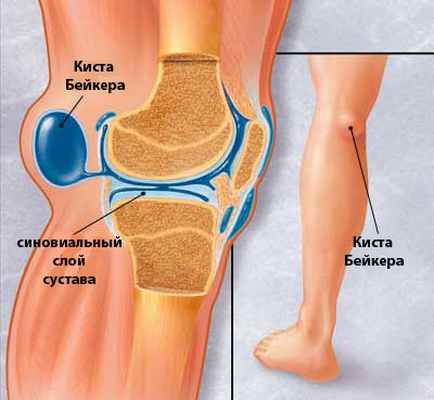

Подколенный бурсит

Подколенный бурсит (киста Бейкера). Особенностью подколенной серозной сумки является то, что в половине случаев она соединяется с полостью коленного сустава, поэтому в большинстве случаев гонартрит и подколенный бурсит развиваются одновременно. Причинами первичного подколенного бурсита являются травмы, микротравмы, перегрузка коленного сустава (в частности при нарушении статики), вторичного— ревматоидный артрит, гонартроз с реактивным синовитом и другие заболевания коленного сустава.

Киста Бейкера проявляется умеренными болями в подколенной ямке, усиливающимися при разгибании голени, иногда слабостью и онемением конечности (сдавление проходящего здесь большеберцового нерва). Подколенная ямка заполнена округлой эластичной опухолью, исчезающей при сгибании голени. Разгибание коленного сустава болезненно и ограничено. Иногда опухоль распространяется на верхнюю часть икроножной мышцы. При пункции кисты получают прозрачную жидкость, напоминающую синовиальную. Часто одновременно наблюдаются признаки артрита коленного сустава.